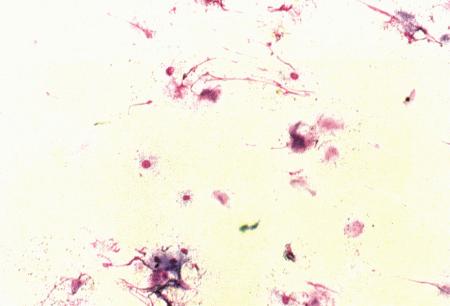

Вагинальная цитология

Повышение концентрации эстрадиола в период проэструса стимулирует деление клеток в базальных слоях вагинального эпителия, но затем концентрация эстрадиола, а соответственно и эндокринная поддержка образования нового, многослойного эпителия снижается, поэтому в образце обнаруживается больше мертвых ороговевших клеток. По мере развития проэструса снижается количество эпителиальных клеток, содержащих ядро. С начала до середины проэструса в вагинальных мазках обнаруживают повышенное содержание эритроцитов. Пик ороговения совпадает с началом повышения концентрации прогестерона; однако в начале эструса исследование не обнаруживает характерных особенностей, которые могли бы указывать на начало фертильного периода. Как правило, такой период наступает несколькими днями позже (табл. 1.1). Тем не менее вагинальная цитология остается популярным методом определения репродуктивного статуса суки из-за своей дешевизны, простоты и доступности. Для получения образца используют ватный тампон, предпочтительно небольшой, который вводят во влагалище и осторожно берут мазок. Полученные клетки помещают под микроскоп, а затем окрашивают контрастным (трихромом) или неконтрастным (например, препаратом Diff-Quik) веществом. При таком окрашивании мертвые кератинизированные клетки становятся оранжевыми, тогда как активные ядерные клетки, а также базальные и парабазальные эпителиальные клетки приобретают различные оттенки от голубого до зеленого.

Ближе к окончанию эструса вагинальные выделения претерпевают характерные изменения (снова выявляются эпителиальные клетки, содержащие ядро, и появляется большое количество лейкоцитов). Такая картина обычно наблюдается через 7–9 дней после пика ЛГ и известна как «вагинальный мазок метэструса». Изменению характера выделений предшествует переходный период, характеризующийся возрастающим количеством активных клеток и указывающий на окончание фертильного периода и эструса (табл. 1.1).

Вагинальная цитология весьма информативна в плане определения фазы эстрального цикла, однако значительные расхождения во времени появления основных признаков эструса по отношению к пику фертильности ограничивает применение указанной методики.

Фиг. 2.2.

Вагинальные выделения кошки (а). Выделения, типичные для фазы эструса. Большая часть клеток представляет собой безъядерные кератинизированные клетки или клетки с пикнотическим ядром. Присутствуют промежуточные клетки (b). Выделения, характерные для метэструса, — «течки», иногда наблюдаемой у кошек в конце эструса. Присутствуют поверхностные и промежуточные клетки, повышено содержание лейкоцитов. Этот короткий метэструс наблюдается в течение 24–48 часов (см. Приложение)